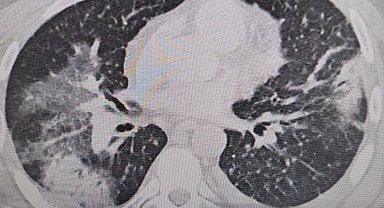

Klimaya bağlı "yaz zatürresine" dikkat